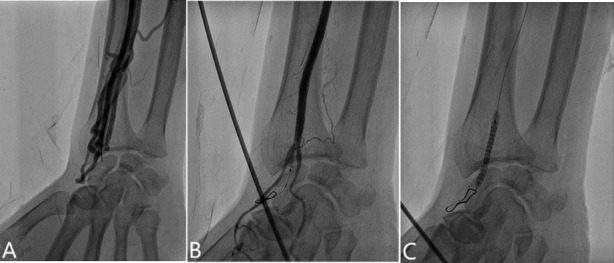

桡动脉动静脉瘘(AVF)在桡动脉介入治疗后极为罕见。在这里,我们报告一个73岁的男性病例,他因急性心肌缺血综合征入院,并接受了左前降支和旋支近端经桡动脉血管成形术。14个月后,患者表现为进行性肿胀,浅表静脉扩张,可触及的震颤,持续的摩擦和局部刺痛。多普勒超声(DUS)诊断桡骨AVF伴多瘘性交通引流至头静脉,经对比增强计算机断层扫描(CECT)证实。尝试使用长时间压缩绷带(bbb12小时)和DUS探头进行局部压缩,但仍然无效。将2.8 × 26 mm Graftmaster支架(Abbott Vascular, USA)经肱入路置于桡动脉瘘颈处,在12 atm压力下缓慢扩张60秒,并在15 atm压力下用3 × 15 mm非顺应性球囊进行扩张。术后血管造影显示瘘完全闭合,掌弓灌注恢复。这是首次报道的使用覆盖支架经肱入路成功排除RAVF的病例,也是第二次使用支架移植经皮排除RAVF的病例。

Radial arteriovenous fistula (AVF) following radial intervention is exceedingly scarce. Here, we report a case of a 73-year-old man who was admitted with acute myocardial ischaemic syndrome and underwent transradial angioplasty of the proximal left anterior descending and circumflex artery. Fourteen months later, he presented with progressive swelling, dilated superficial veins, a palpable thrill, continuous bruit, and tingling at the local site. Doppler ultrasonography (DUS) diagnosed radial AVF with multiple fistulous communications draining into the cephalic vein, confirmed by contrast-enhanced computed tomography (CECT). Local compression using a prolonged compressive bandage (>12 hours) and a DUS probe was attempted but remained ineffectual. A 2.8 × 26 mm Graftmaster stent graft (Abbott Vascular, USA) was deployed into the radial artery across the fistula neck via a transbrachial approach, slowly expanded over 60 seconds at 12 atm pressure, and post-dilated with a 3 × 15 mm noncompliant balloon at 15 atm pressure. A post-procedure angiogram displayed complete closure of the fistula with restoration of palmar arch perfusion. This is the first reported case of successful exclusion of RAVF through transbrachial approach using a ever covered stent, and only the second case overall of percutaneous exclusion using a stent graft.